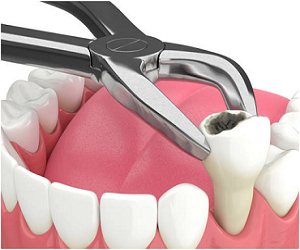

Emergency Case

Emergency dental care may be needed if you have had a blow to the face, lost a filling, or cracked a tooth.

"Perfect one stop solution for all Dental problems by experienced dentist, rct specialist, braces treatment, dental implant, cosmetic dentist , Orthodontist , gum problem, laser dentistry, teeth whitening , tooth surgery"